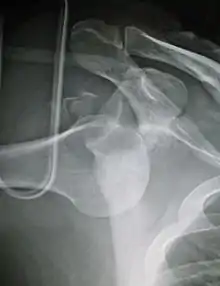

Anterior dislocation of the left shoulder.

X-ray at left shows anterior dislocation in a young man. X-ray at right shows the same shoulder after reduction and internal rotation, revealing a Bankart lesion and a Hill-Sachs lesion.

In over 95% of shoulder dislocations, the humerus is displaced anteriorly.[6] In most of those, the head of the humerus comes to rest under the coracoid process, referred to as sub-coracoid dislocation. Sub-glenoid, subclavicular, and, very rarely, intrathoracic or retroperitoneal dislocations may also occur.[7]

A Hill–Sachs lesion is an impaction of the head of the humerus left by the glenoid rim during dislocation.[5] Hill-Sachs deformities occur in 35–40% of anterior dislocations. They can be seen on a front-facing X-ray when the arm is in internal rotation.[8] Bankart lesions are disruptions of the glenoid labrum with or without an avulsion of bone fragment.